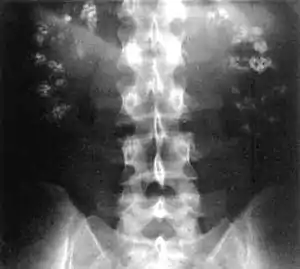

| Significant bilateral nephrocalcinosis (calcification of the kidneys) on a frontal X-ray (radiopacities (white) in the right upper and left upper quadrant of the image), as seen in distal renal tubular acidosis | |

- Nephrocalcinosis (deposition of calcium in the substance of the kidney)

- Bone demineralisation (causing rickets in children and osteomalacia in adults